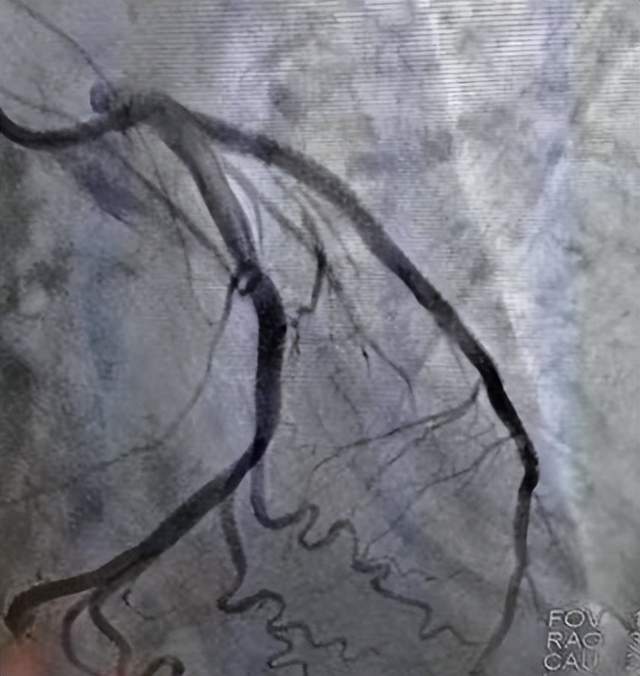

经过紧张的抢救,医护人员于11时58分成功完成了急诊冠脉造影,结果显示刘伯的前降支近段完全闭塞。12时16分成功通过导丝。然而,在植入支架的过程中,刘伯再次出现了室速、室颤等严重症状,手术医生迅速判断为电风暴,并再次进行同步电复律、电除颤等处理,最终成功在罪犯血管植入了支架,开通了患者的“生命通道”。